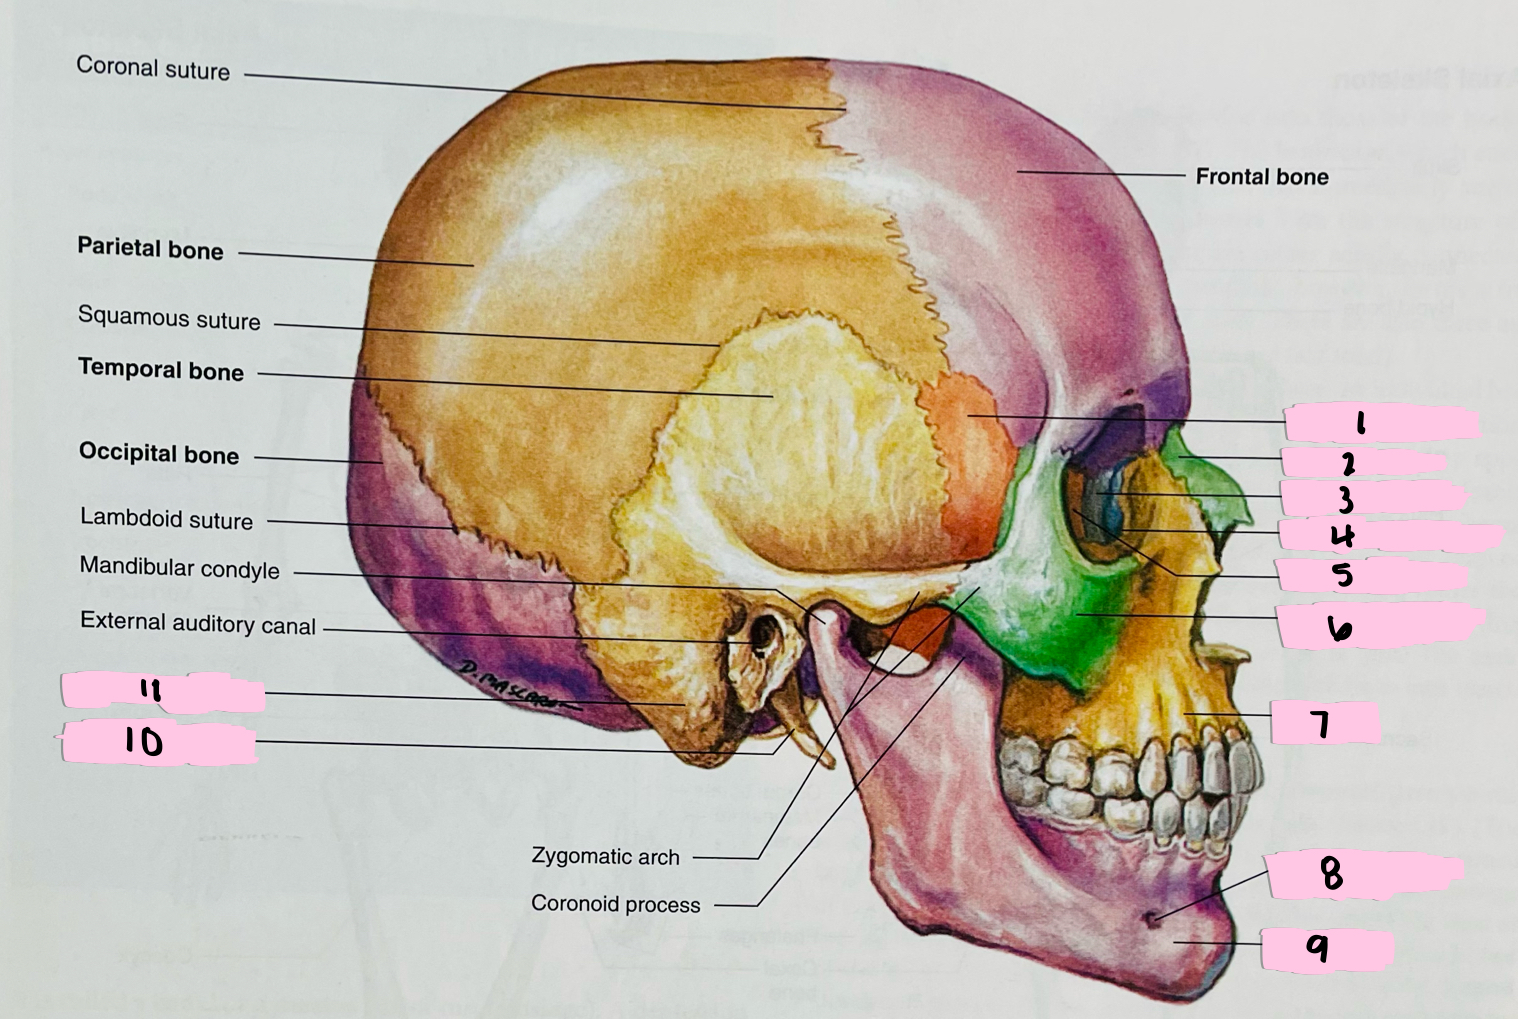

What is 1 pointing to?

Sphenoid bone

What is 2 pointing to?

Nasal bone

What is 3 pointing to?

Lacrimal bone

What is 4 pointing to?

Nasolacrimal canal

What is 5 pointing to?

Ethmoid bone

What is 6 pointing to?

Zygomatic bone

What is 7 pointing to?

Maxilla

What is 8 pointing to?

Mental foramen

What is 9 pointing to?

Mandible

What is 10 pointing to?

Styloid process

What is 11 pointing to?

Mastoid process